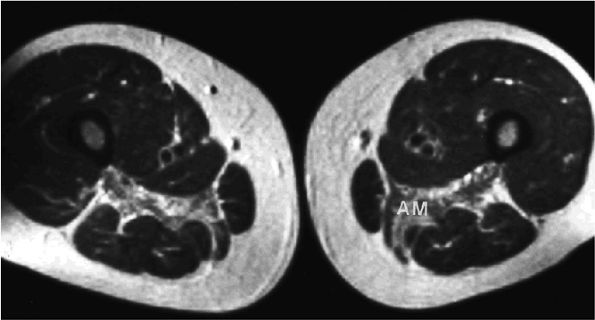

FIGURE 3.106 ● Bilateral adductor longus grade 1 muscle strain with diffuse hyperintense muscle edema. Coronal FS PD FSE image.